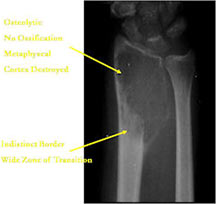

- Permeative lesion with indistinct border that is poorly marginated

- Osteolytic and expansile on X-ray with very little osteoid production

- Osteoid usually not discernible on X-ray but scant and faint lace-like osteoid may be detectable on a CT scan

- No surrounding sclerosis

- May have Codman’s triangle and malignant appearing periosteal reaction in most cases

- Cortical destruction and soft tissue extension are common

- Expands contour of bone and may appear similar to an ABC (aneurysmal bone cyst)